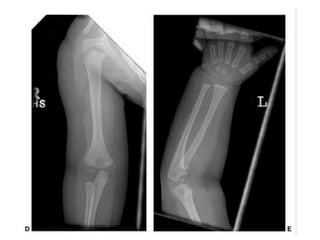

Decreased arm span and standing

height—Rhizomelic shortening

fingertips usually reach only to the

tops of the greater trochanters

flexion contracture of the elbows

Kyphosis at the DL junction Lumbar lordosis increases